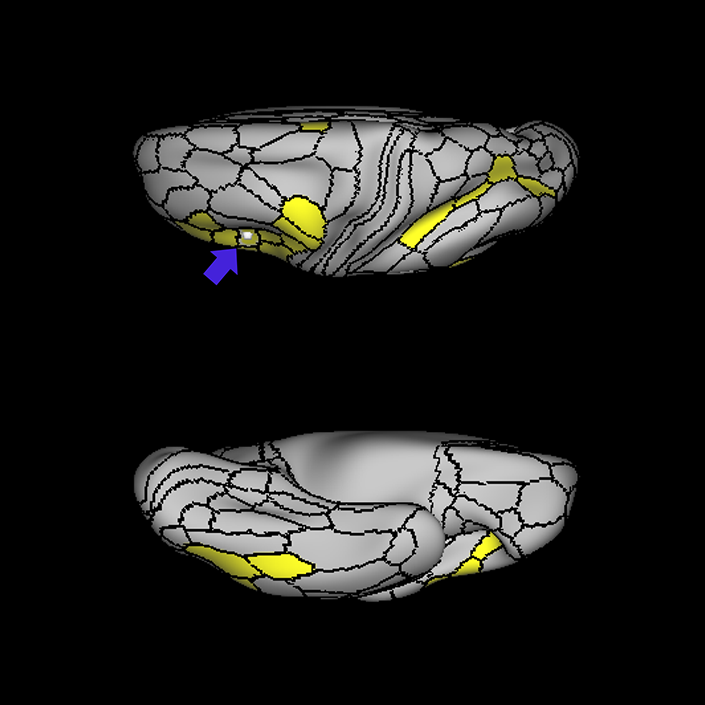

ᐅ SummaryArea 45: part of the inferior frontal gyrus of the lateral frontal lobe. In addition to its known association with Broca's area, is sometimes represented as part of Broca's complex ᐅ Where is it?Area 45 is the lateral surface of pars triangularis of the IFG. ᐅ What are its borders?Area 45 borders area 47L anteriorly and area 44 posteriorly. Its superior edge borders area p47r, IFSa, and IFSp. Its opercular surface is conveniently named FOP5 ᐅ What are its functional connections?Area 45 demonstrates functional connectivity to areas SFL, IFSp, 44, a47r, 47s, 47L, 9a, 9p, 9m, 8AV, and 8BL in the dorsolateral frontal lobe, area 8BM in the medial frontal lobe, area 55b in the premotor areas, areas FOP5, and PSL in the insula-opercular region, areas TGd, TGv, TE1a, STSva, STSdp and STSvp in the temporal lobe, area PGi in the inferior parietal lobe, and area 31pd in the medial parietal lobe. ᐅ What are its white matter connections?Area 45 is structurally connected to the arcuate/SLF and IFOF. However, arcuate/SLF connections are not consistent across individuals. Connections with the arcuate/SLF project posteriorly and wrap around the Sylvian fissure to the middle temporal gyrus to end at TE1p. There are also projections from the arcuate/SLF before it terminates to parcellations A4 and PBelt. IFOF connections travel from 45 through the extreme/external capsule and continue posteriorly through the temporal lobe to end at occipital lobe parcellations V1, V2, V3 and V4. Local short association bundles connect with 44 and FOP4. ᐅ What is known about its function?Area 45, in addition to its known association with Broca's area, is sometimes represented as part of "Broca's complex", including Brodmann Areas 45, 46, 47 and the mesial supplementary motor area of 6, which contribute to a frontal-subcortical circuit. |

A: lateral-medial

B: anterior-posterior

C: superior-inferior

DTI image |